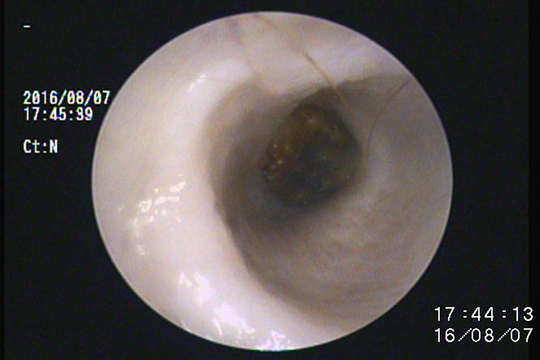

慢性外耳炎の耳の中です。

掻く刺激と、耳内の環境悪化に伴い耳道が腫れて狭くなっています。

繰り返す外耳炎で耳道壁がボコボコと不整になっています。

耳垢腺という分泌組織が増殖し、より耳垢や細菌の温床になります。

このような場合はしっかりと鼓膜まで耳垢を除去し、菌の種類を特定し、適切なお薬を使用して管理します。

中耳炎を併発していることが多いケースです。